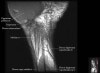

- Coronal section

Coronal T1 imaging evaluates bone marrow signal (ex. increased in avascular necrosis) and the relationship of the osseous structures to each other (ex. scapholunate disassociation).